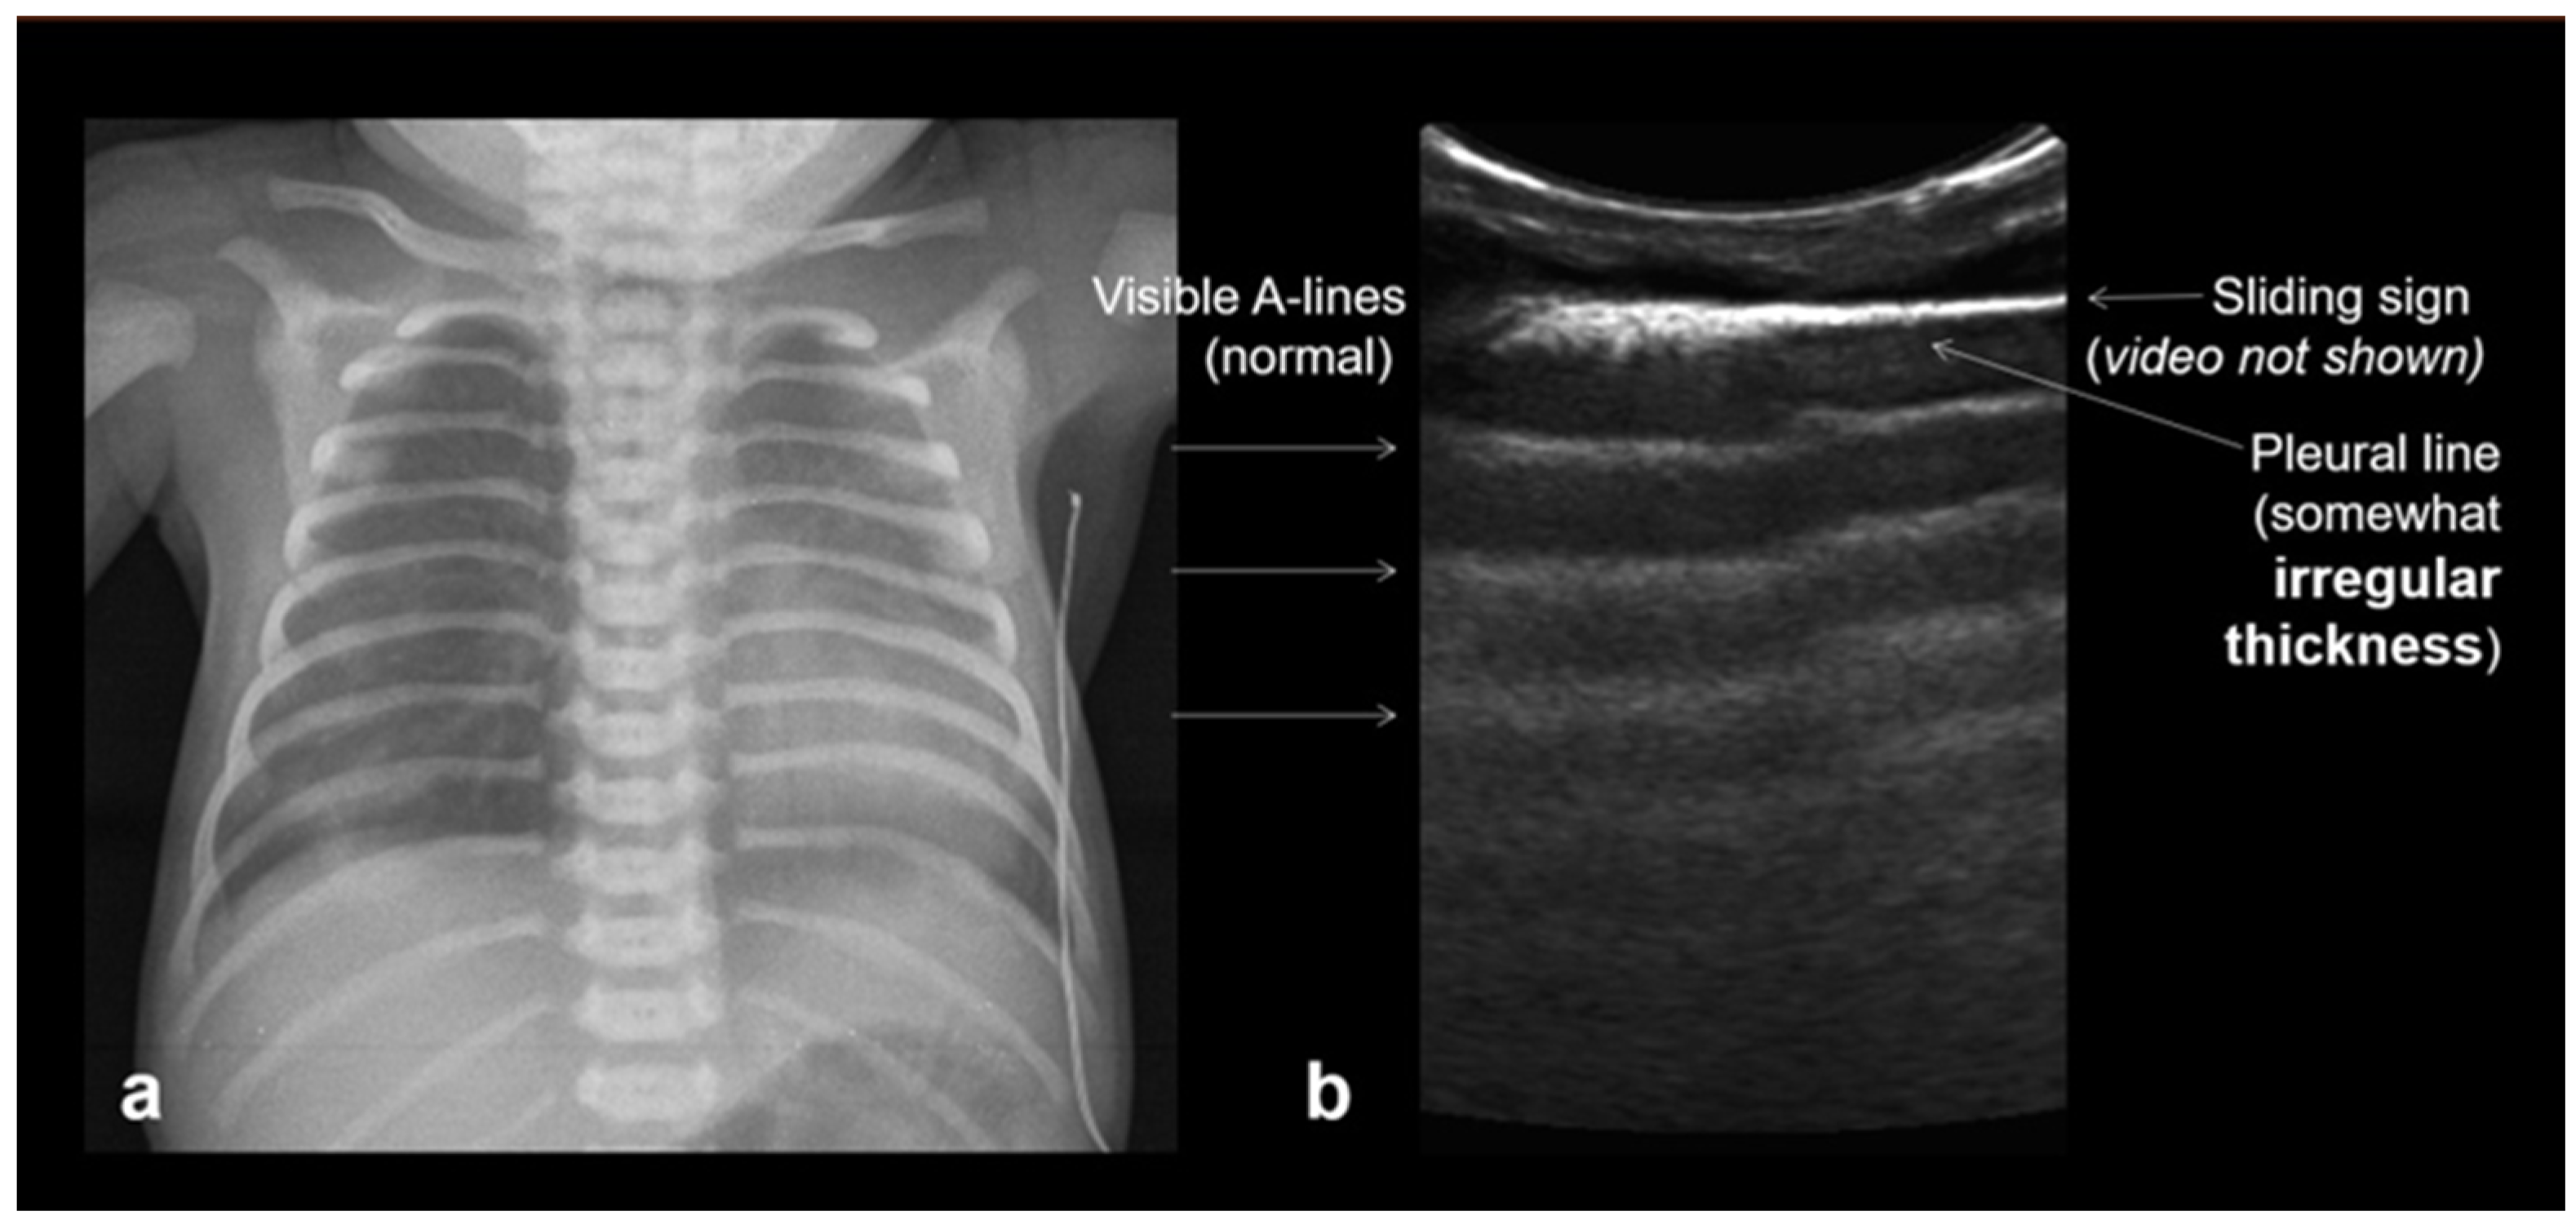

In RDS, lung ultrasound findings include consolidation or bilateral “white lung”, aero bronchograms, pleural line abnormalities, and the absence of A-lines (Figure 12, Figure 13, Figure 14 and Figure 15) [30,35,40,41].

Figure 12.

A frequent and characteristic imaging finding in RDS is the presence of B-Lines, bilaterally and throughout the lung parenchyma, in this case bilateral B-lines with no normal parenchyma (a) (absence of A-lines). Also, note the abnormal thickening ((a,b) arrows) of the pleural line (b). The overall sense is that of white lung.

Figure 13.

Normal to mild RDS: by chest X-ray (a); by LUS (b).

Figure 14.

Severe RDS shown on chest X-ray (a); LUS (b). The ability of the LUS to characterize the severity of the RDS is debatable.

RDS is a common cause of neonatal respiratory failure, particularly in preterm infants, resulting from surfactant deficiency and alveolar collapse. LUS has become a valuable diagnostic tool for RDS, offering real-time visualization of lung pathology at the bedside [38,42,43,44,45]. A hallmark sonographic feature of RDS is the presence of dense, confluent B-lines throughout the lung fields, producing a “white lung” appearance due to the loss of normal aeration. Notably, the whole lung is typically involved, with a diffuse, bilateral distribution that distinguishes RDS from more localized pulmonary conditions [37,46,47]. Additionally, interspersed consolidations may be present, including hypoechoic and subpleural areas of alveolar collapse, reflecting regions of complete de-aeration. These consolidations often lack air bronchograms and are associated with irregular or thickened pleural lines. The combination of diffuse B-line patterns, global lung involvement, and patchy consolidations provides a highly suggestive ultrasound profile of RDS and facilitates early diagnosis. In addition, for RDS, LUS may be used for severity assessment and the monitoring of treatment response in the neonatal intensive care setting [16,20,27,29]. The ability of the LUS to characterize the severity of the RDS is debatable (Figure 14 and Figure 16) [48].